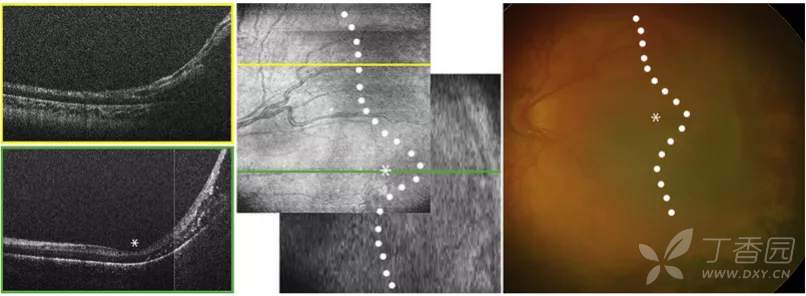

ROP 1至3期OCT图像

图. OCT图像上的1期分界线(白箭)与视网膜血管-无血管连接处对齐。

图. OCT图像上的2期脊(白箭)表现为视网膜内层局灶性增厚、隆起,与en face图像上血管区-无血管区交界处较宽的暗边界一致。

图. OCT图像和en-face图像显示3期视网膜外新生血管形成(白箭)。

急性ROP4期OCT图像

图. 4A期视网膜脱离:OCT可见中心凹视网膜附着(星号),视网膜内渗出(高反射点)、周边部视网膜脱离和视网膜劈裂。

图. 4B期视网膜脱离:OCT可见中心凹视网膜脱离(星号),在检眼镜检查中很难识别。